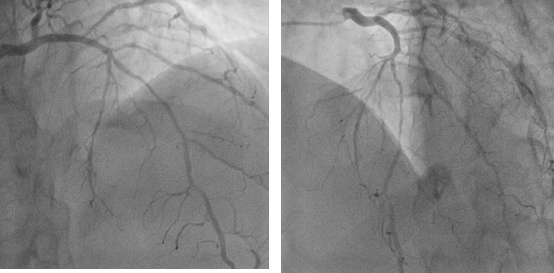

冠動脈疾患は誰もが知っている病気であり、多くの冠動脈疾患患者が心臓ステントを装着している。 現在、心臓ステントは、冠動脈が75%以上閉塞し、重度の狭心症の症状を伴う患者の症状を改善し、生存率を高めるための良い選択である。現在、心臓ステントには主にベアステント、薬剤溶出ステント、分解性ステントの3種類がある。一般的に使用されているベアステントと薬剤溶出性ステントは金属ステントによって支えられており、心臓にステントを留置した人は、外が雨や雷雨になると心臓ステントに危険が及ぶことが懸念されています。これは本当でしょうか?

心臓ステントは、狭窄または閉塞した血管を開かせるために血管内に留置される薄い金属製のかごのように見える。 閉塞した血管がスムーズに流れるようになり、心臓への血液供給が増加し、心筋壊死の程度が軽減される。心臓ステントは実際には非常に小さく、直径2~4mm、長さわずか数cmで、通常はチタン合金製の中空の円筒形の網目状の金属管である。非常に小さく、移植後は血管内皮に包まれるため、外界の影響を受けない。雷や雨の影響はさらに少ない。